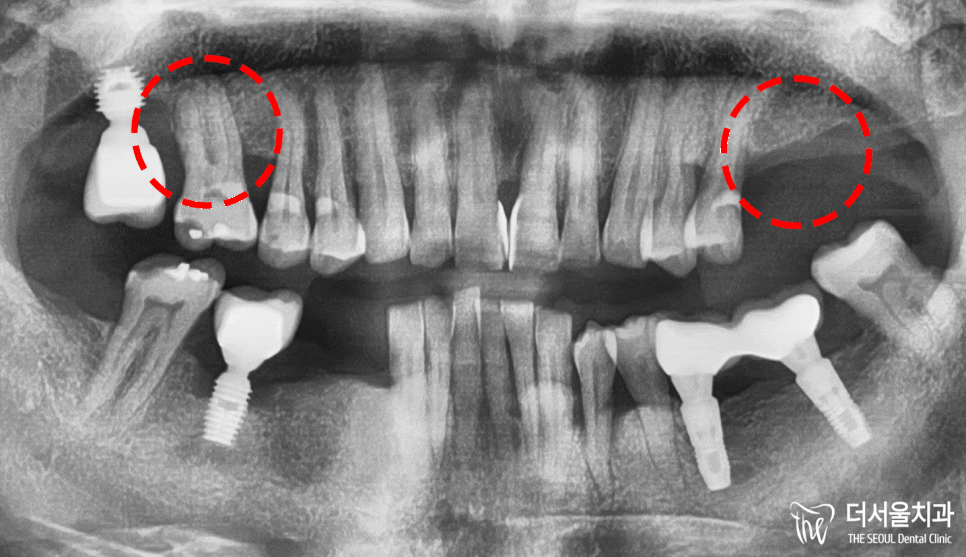

성남 치과 에 첫 내원하셨을 때,

상악 쪽 상태 역시 좋지 않았습니다.

16번은 치조골 소실이 일어나

고정력을 잃고 있었으며,

26, 27번 치아는 이미 상실했었죠.

이미 동요도를 확인했을 때,

심한 흔들림이 있어

빠르게 발치 후 식립이 이뤄지는 게

오히려 더 나은 상황이었습니다.